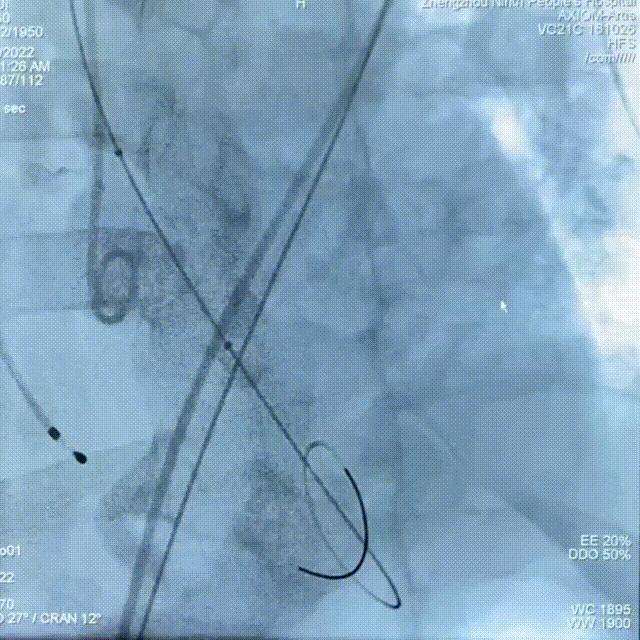

18mm球囊预扩

TAV24瓣膜精准定位

缓慢释放至1/3